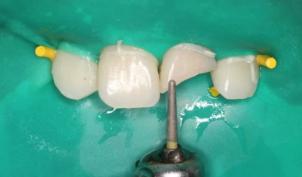

“旧冠再利用”术前牙冠大面积折断,露牙髓:

折断的牙冠:

根管治疗术前、术后:

根管治疗后牙冠重新粘接: